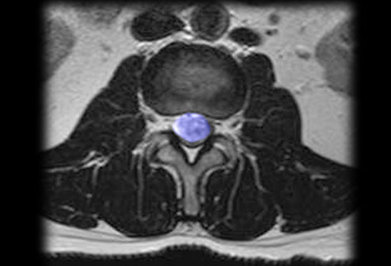

وی در ادامه افزود: تومور تعدادی علائم اختصاصی دارد که به طور معمول در اثر معاینه اختلالات عصبی میتوان محل تومور و نوع آن را مشخص کرد که با عکسبرداری و ام آرای میتوان تومور را تشخیص داد.

وی تصریح کرد: تومور ممکن است درهر سنی رخ دهد معمولا در سن بالا بین 40 تا 60 سال اتفاق میافتد برای درمان از عمل جراحی یا رادیو تراپی استفاده میکنیم.